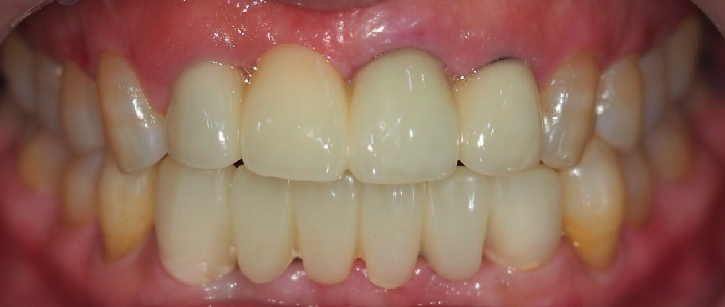

▲ 최종 보철 장착 사진

이렇게 전치부 아래 치아 쪽에 최종 보철을 장착한 모습입니다.

최종 치료 까지는 24. 06.29 ~09.30 총 3개월 소요 되었습니다.